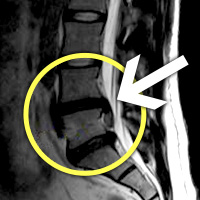

MRI

MRI ġ